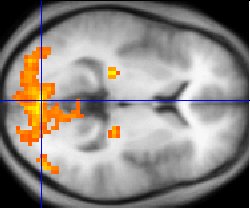

功能MRI(fMRI):看到大脑的"思考"

革命性突破(1990年):

- 发现者:小川诚二(Seiji Ogawa)

- 原理:血氧水平依赖(BOLD)效应 - 大脑活动区域血流增加,氧合血红蛋白比例改变

- 意义:无创观察大脑功能活动

功能MRI(fMRI)脑激活图:彩色区域表示执行特定任务时大脑活跃的区域

主要应用领域:

| 应用领域 | 具体应用 | 临床/科研价值 |

|---|---|---|

| 临床医学 | 术前脑功能定位(语言区、运动区) | 降低手术风险,保护重要功能区 |

| 认知神经科学 | 记忆、注意力、情绪等认知过程研究 | 理解大脑工作机制 |

| 精神疾病 | 抑郁症、精神分裂症、自闭症研究 | 寻找生物标志物,指导治疗 |

| 脑机接口 | 解码大脑活动信号 | 辅助瘫痪患者交流 |

fMRI脑功能图谱:通过统计分析多次任务激活数据,可以绘制出大脑不同功能区域的精细分布图

🧠 fMRI的局限性

虽然fMRI非常强大,但它测量的是血流变化,而不是神经元活动本身。时间分辨率较低(秒级),空间分辨率也有限(毫米级)。因此,它更适合研究"哪里"在活动,而不是"如何"活动。